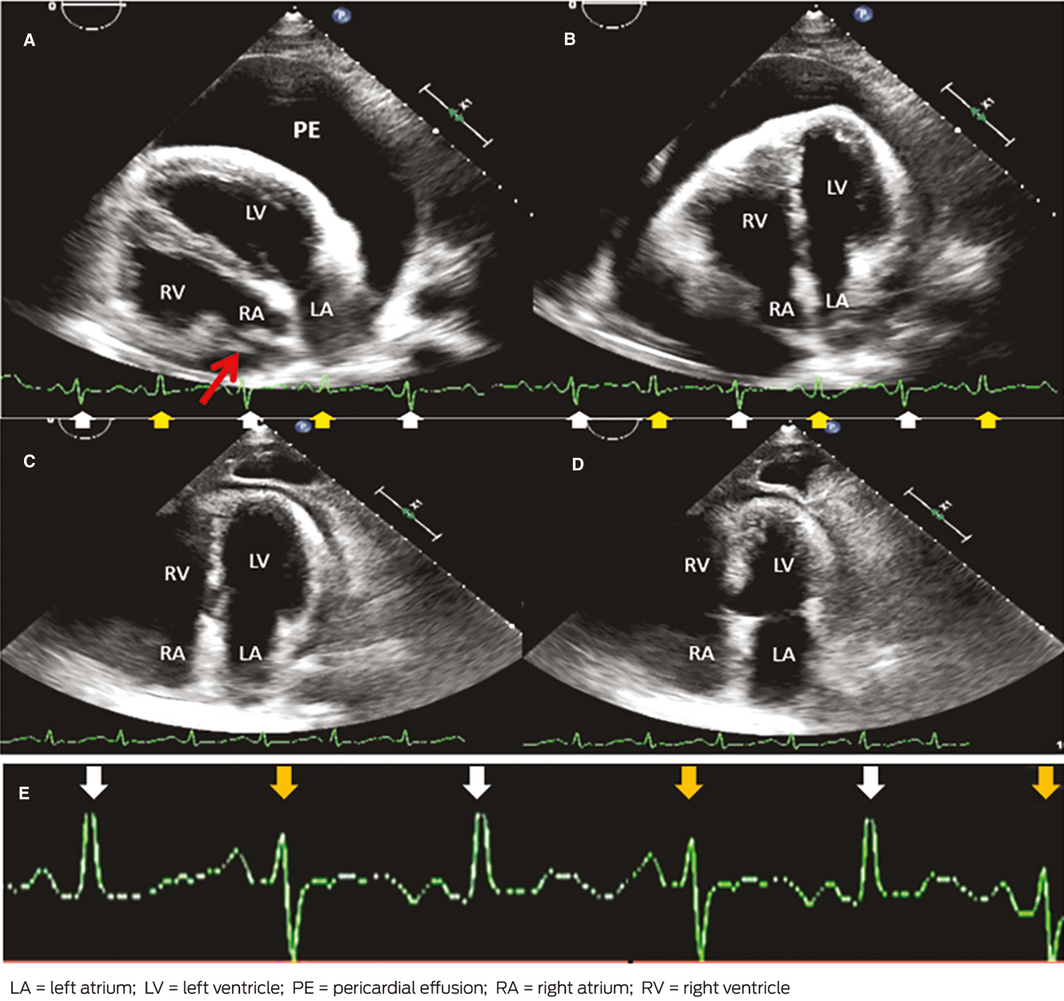

Demonstrating the mechanism of electrical alternans in cardiac tamponade: “the swinging heart”

Med J Aust 2020; 213 (2) || doi: 10.5694/mja2.50687